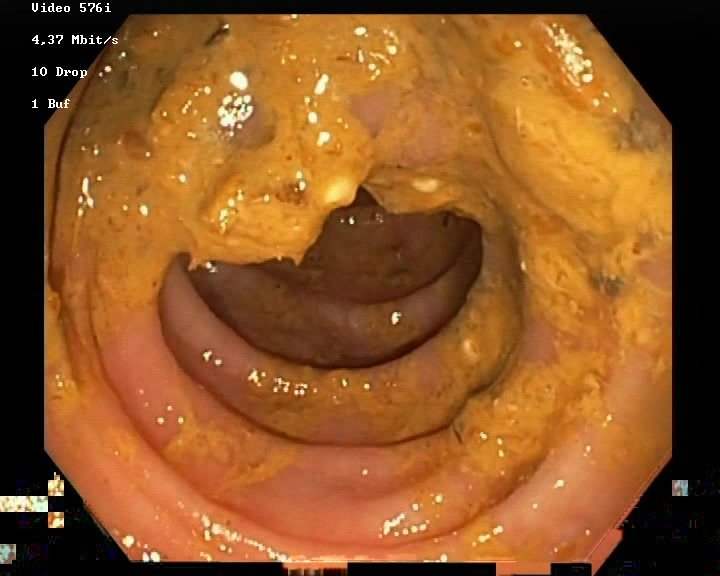

The Nerthus Dataset

BBPS 3

BBPS 2

BBPS 1

BBPS 0